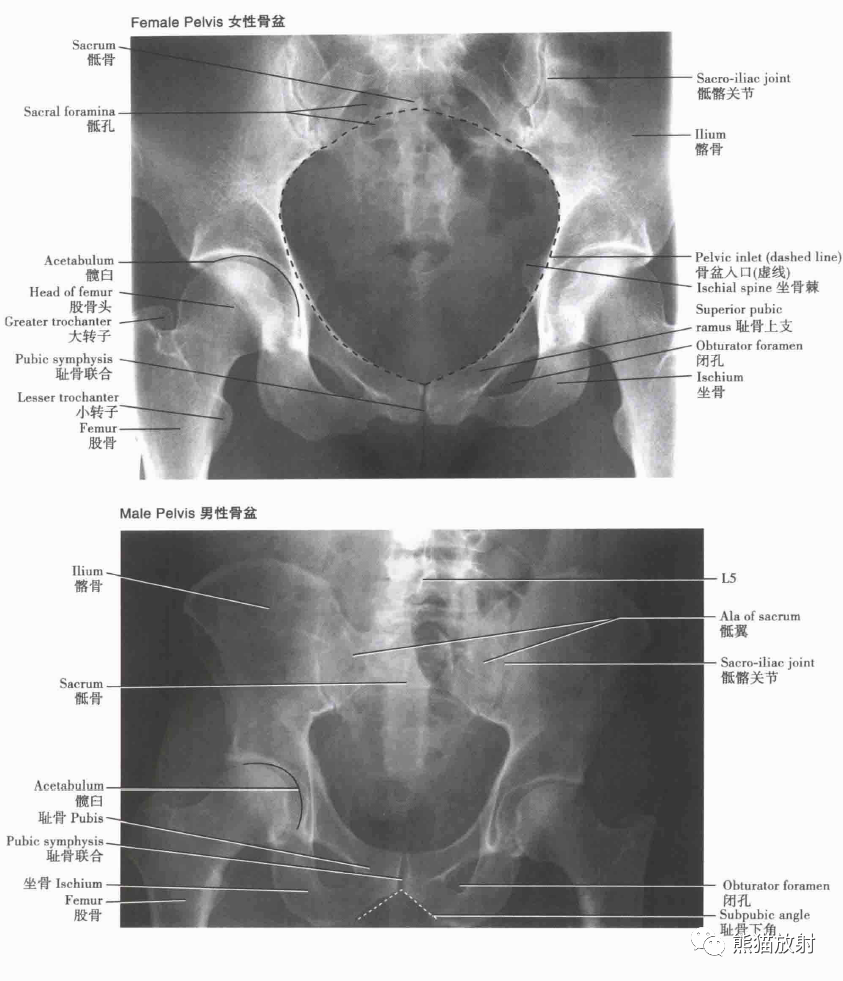

骨盆的骨性结构

男性和女性的骨盆成像

骨盆的性别差异:测量